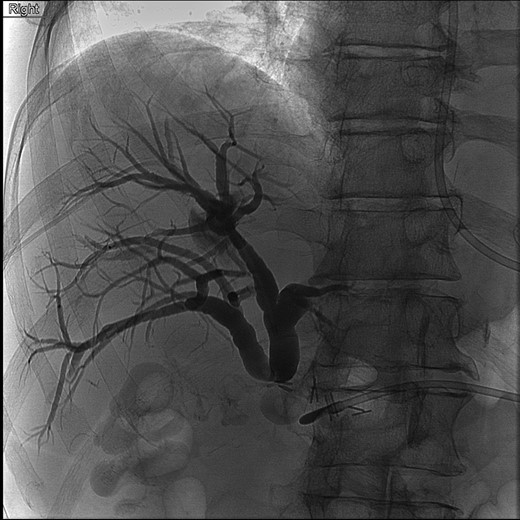

During this operation, the porta was dissected and the common and proper hepatic arteries were identified and preserved. We were unable to palpate the previously placed percutaneous biliary catheters due to the high placement above the hilum at the level of multiple clips. We transected the CBD distally and removed numerous clips, finally noting bile drainage, but were unable to identify a cholangiogram catheter. We then identified a second tubular structure more lateral to the duct. We elected to transect this tissue, identifying a second extrahepatic bile duct. The anterior percutaneous catheter was identified proximally within the duct. An on-table cholangiogram with fluoroscopy was performed noting two separate extrahepatic biliary systems, draining the right and left lobes of the liver, respectively (Figs 3 and 4). Both distal ducts were ligated to definitively close the orifice to the duodenum and prevent spillage. A Roux limb of jejunum was created and anastomosed in a retrocolic fashion to the two separate hepatic ducts at the level of the hilum. A drain was placed, and there was no evidence of bile leakage.

Intraoperative cholangiogram of the right ductal system through the extrahepatic right CBD.

Intraoperative cholangiogram of the left ductal system through the extrahepatic left CBD.